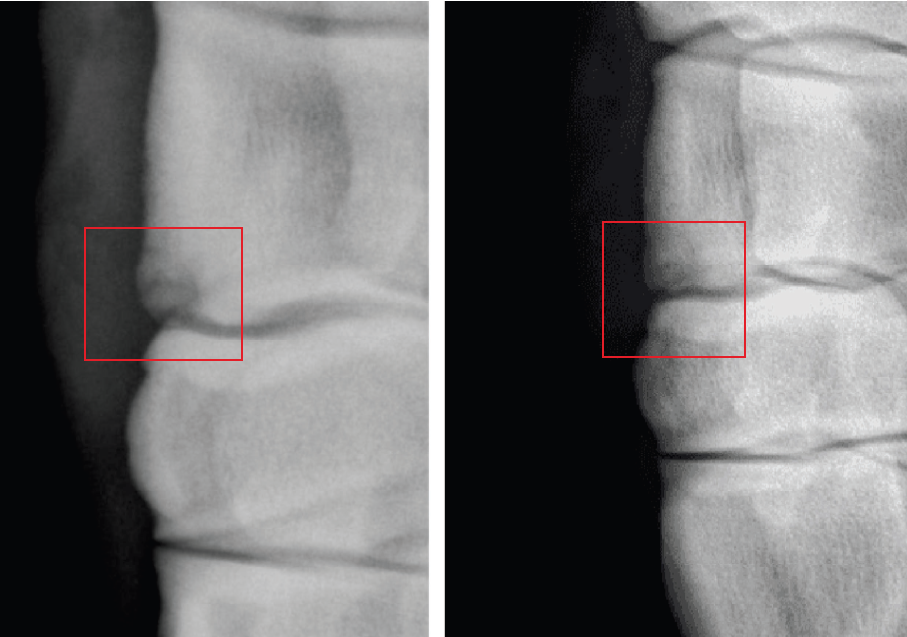

In 2023 a thoroughbred yearling was disqualified from sale due to a severe Osteochondritis Dissecans (OCD) lesion in her knee. The breeder was informed that the lesion was so severe, and in such a difficult position that surgery was not possible and that the horse would never race.

After OBET treatment the final radiograph interpretation reflected ‘Remodeling of distal dorsal aspect of radial carpal bone, no fragment seen.’ NSA – No significant abnormalities.

The horse is now in active race training.